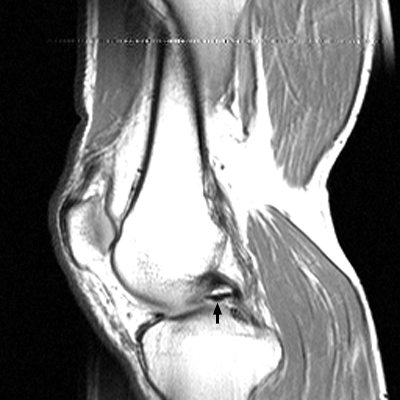

Multiple sagittal T1 weighted images which reveal loss of the normal bow-tie appearance of the meniscus. The "absent bow tie sign" is another good sign of a bucket handle tear of the meniscus. The absence of the normal bow-tie is secondary to the displaced fragment which makes up the "handle" of the bucket. Requirement for the absent bow tie sign mandates that the normal requirement of at least two adjacent sagittal images with a normal meniscal body segment appearance is not present.

- Click on the image for a larger versionA - Click on the image for a larger versionB - Click on the image for a larger versionC